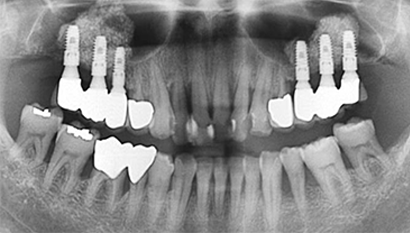

W Dental Clinic Before & After

치료 전후사진

After

상악동 거상술